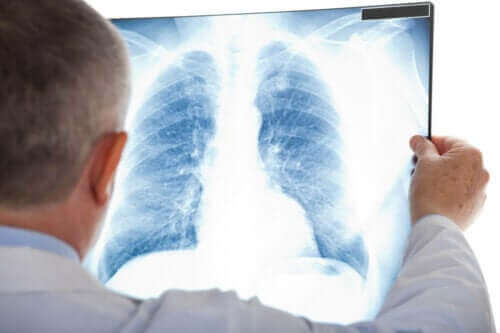

비정형 폐렴의 경우 일반적으로 숨을 쉴 때 쌕쌕거리는 소리가 난다. 바람과 비슷한 소리가 난다. 때때로 그것은 감염을 종종 동반하기 때문에 흉부 엑스레이를 촬영한다.